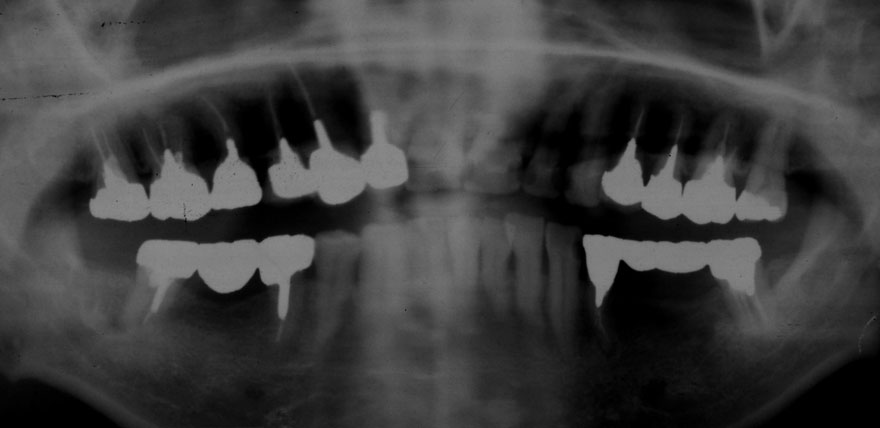

初診時 41歳 男性 平均歯槽骨喪失量:4.11mm

30年後 71歳

平均歯槽骨喪失量:3.70mm

30年間再生量:+0.41mm

年間再生速度:+0.014mm

(ケア頻度:1.27ヵ月ごと)